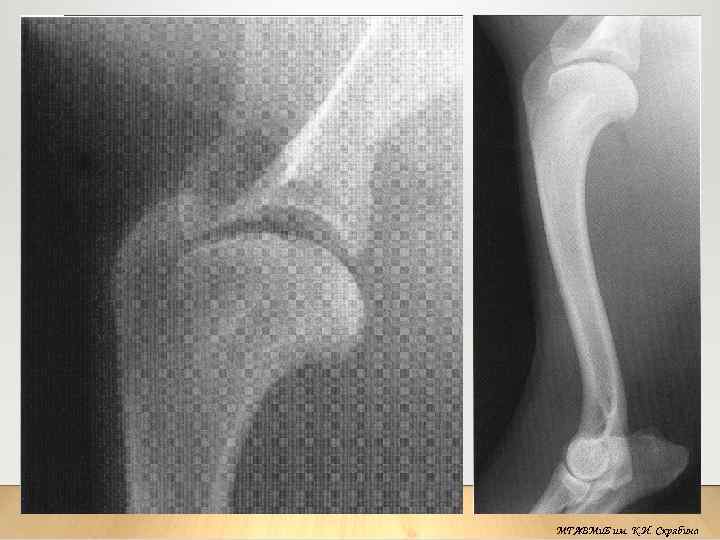

Рентгеноанатомия

МГАВМи. Б им. К. И. Скрябина